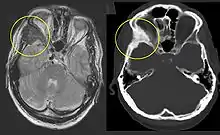

الأشعة ببلي السينية للآفة الخلوية / اختبارات التصوير الزجاجي الأرضي. يمكن استخدام التصوير المقطعي المحوسب أو التصوير بالرنين المغناطيسي لتحديد مدى تأثر عظامك. فحص العظام. يستخدم هذا الاختبار أجهزة تتبع إشعاعية، يتم حقنها في مجرى الدم. تستهلك الأجزاء التالفة من عظامك المزيد من أجهزة التتبع، والتي تظهر بشكل أكثر سطوعًا على المسح. خزعة. يستخدم هذا الاختبار إبرة مجوفة لإزالة قطعة صغيرة من العظام المصابة للتحليل المختبري.